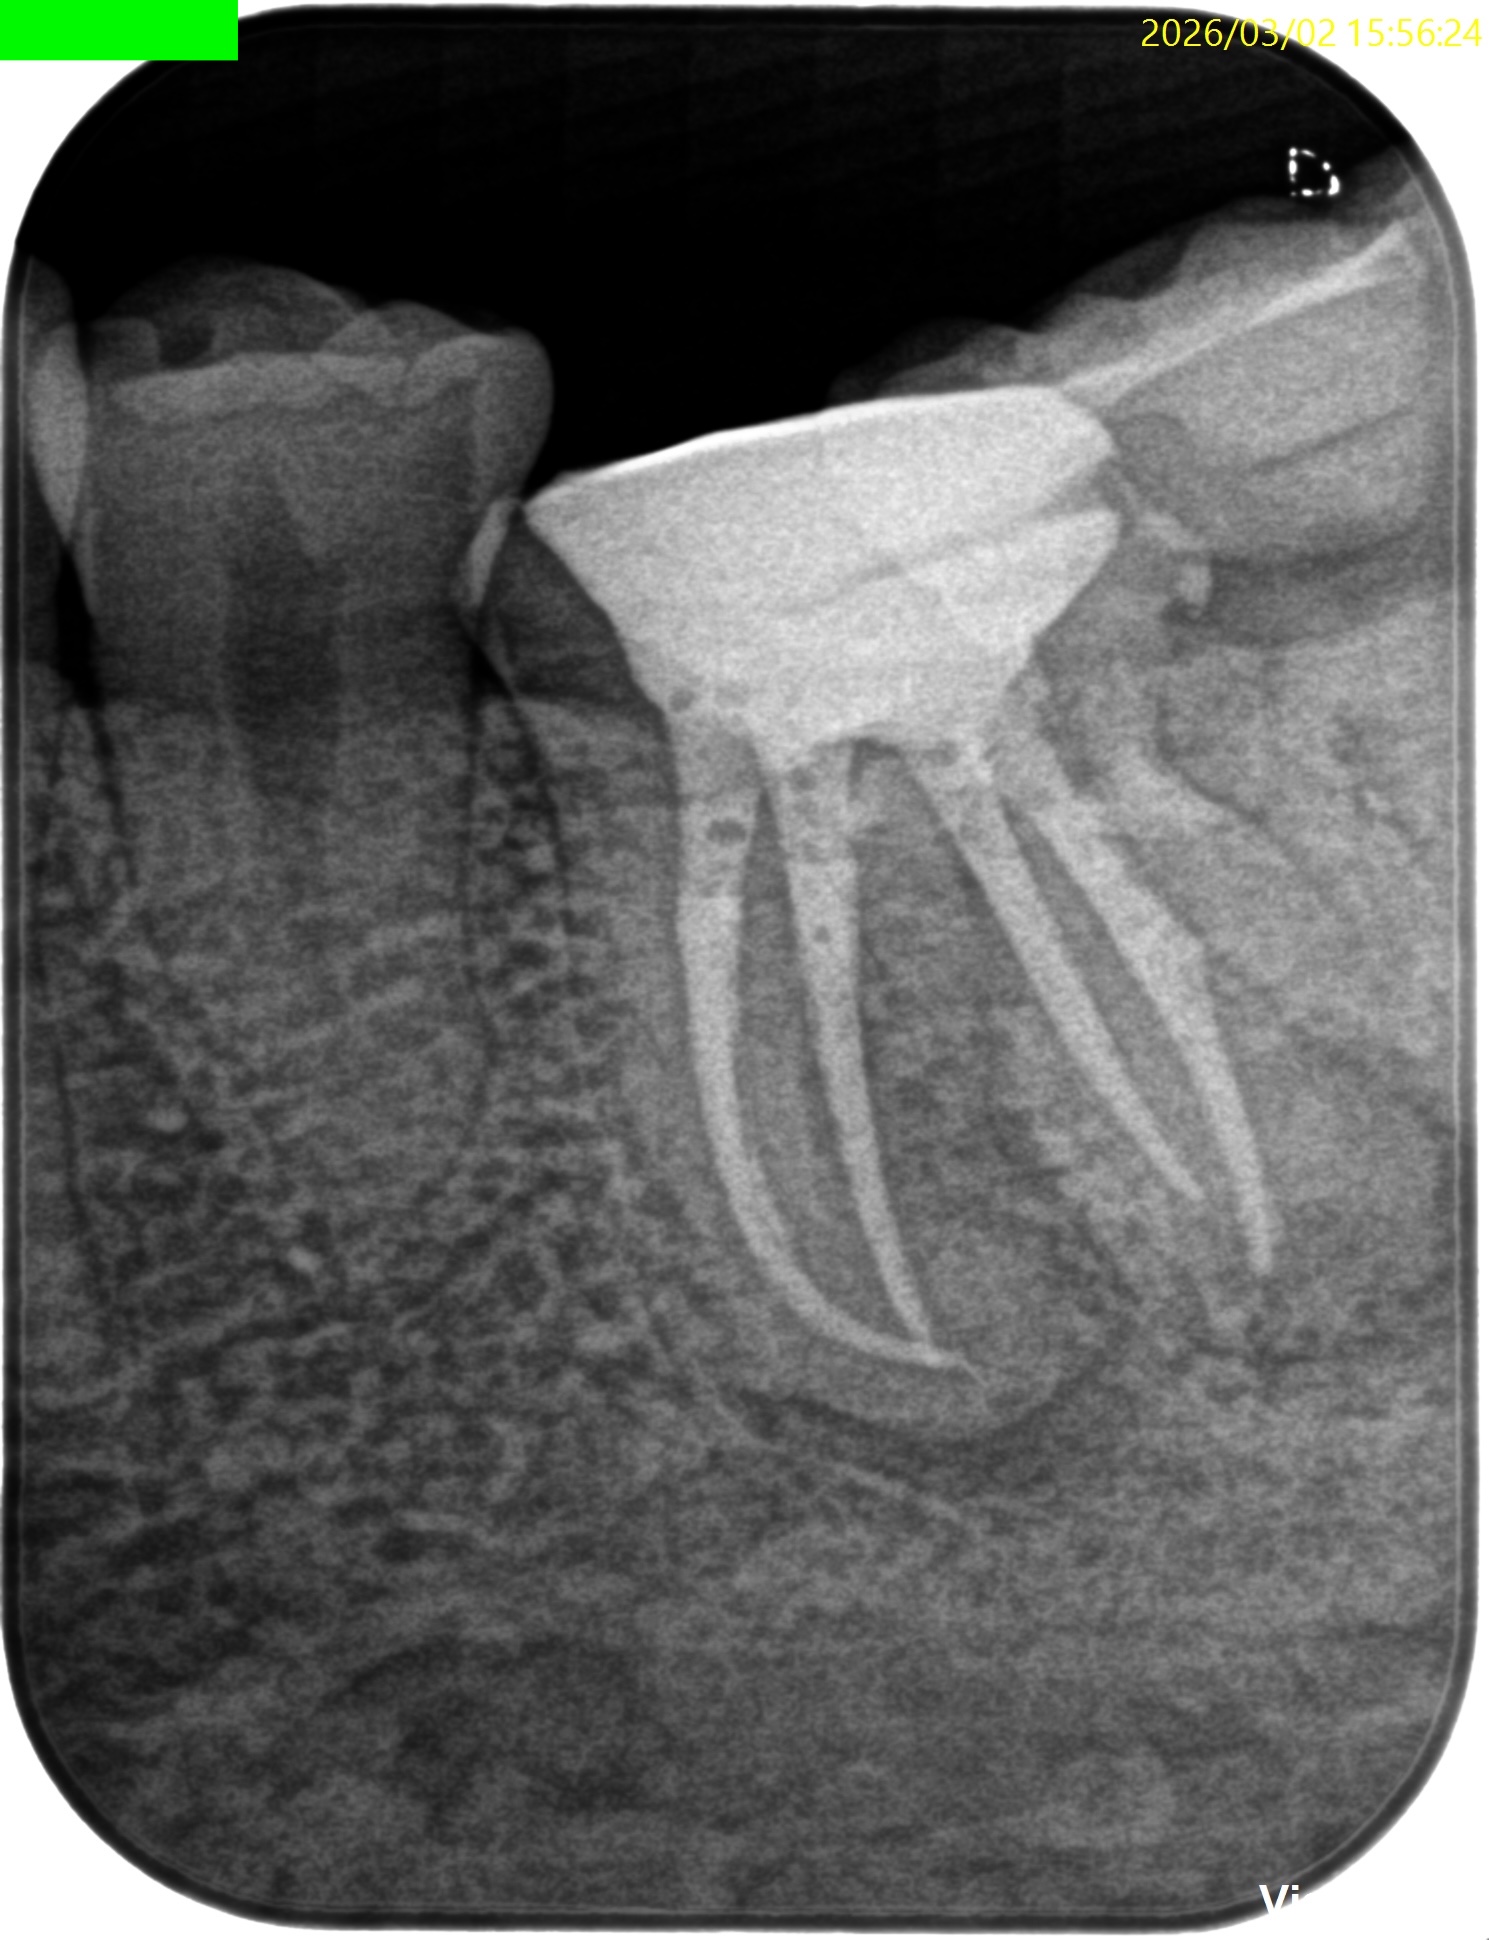

DB

DL

B